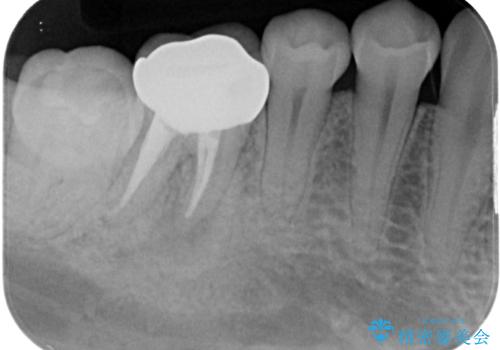

- 奥歯の虫歯を心配して来院した患者様です。

レントゲン写真から、以前治療した詰め物の下に虫歯があることがわかりました。

精度が高く、虫歯の再発リスクの低いゴールドインレーで治療を行うこととしました。